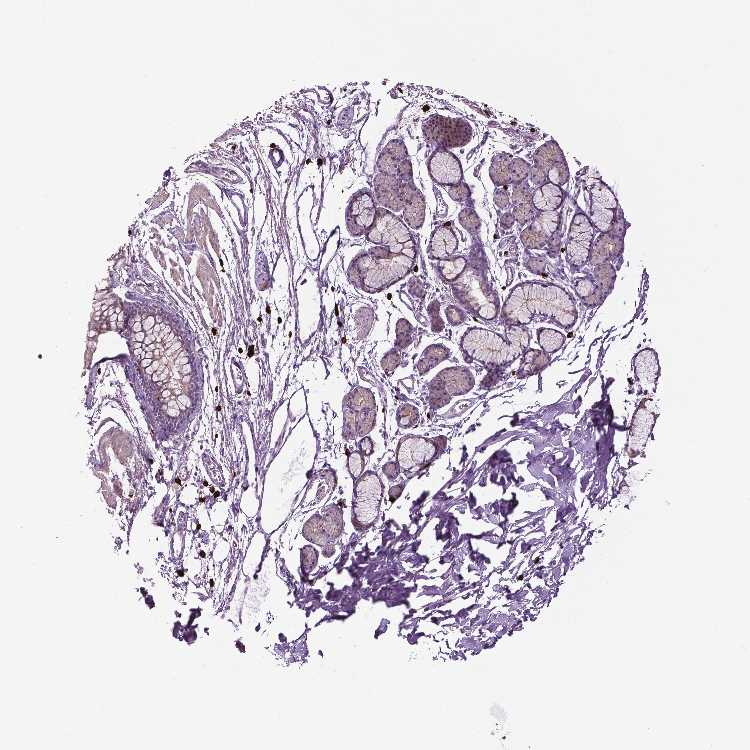

ADIPOSE TISSUE - Antibody stainingi

Antibody staining in the annotated cell types in the current human tissue is reported as not detected, low, medium, or high, based on conventional immunohistochemistry profiling in selected tissues. This score is based on the combination of the staining intensity and fraction of stained cells.

Each image is clickable and will lead to virtual microscopy that enables deeper exploration of all samples and also displays staining intensity scores, fraction scores and subcellular localization as well as patient and tissue information for each sample.

Antibody HPA070614

Adipocytes Not detected